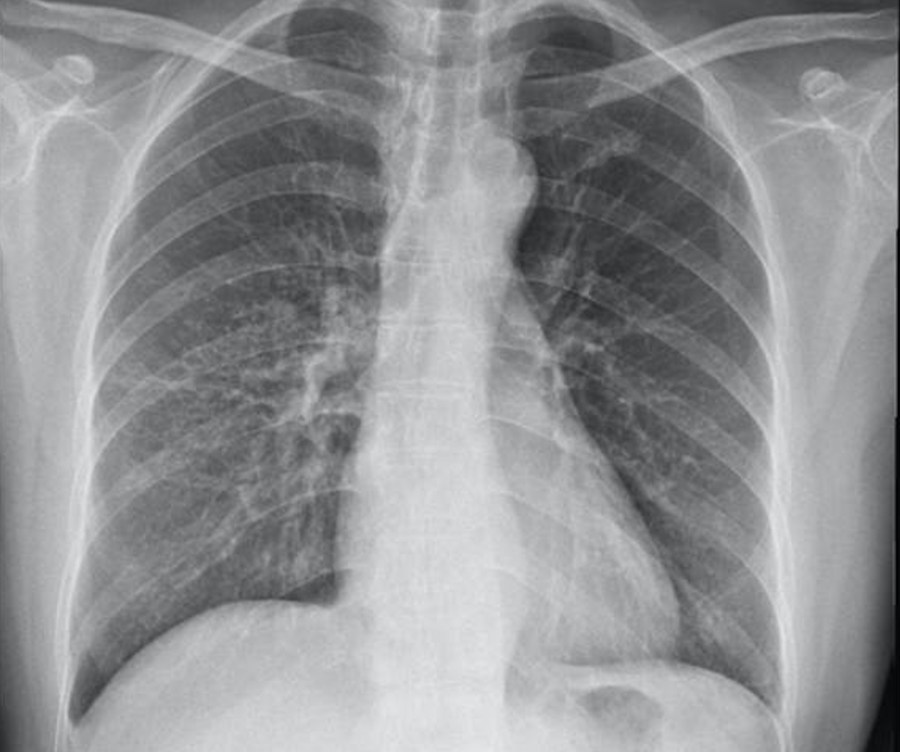

AT-CXR-2016